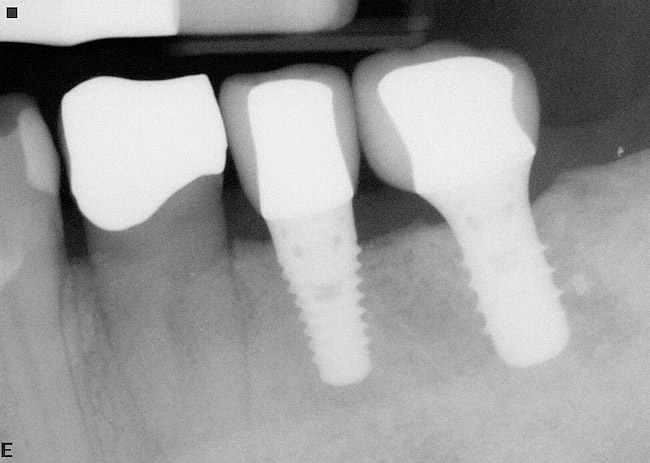

Figure 17  In another case, the mandibular left second molar was fractured and hopeless.

Figure 17

Figure 18  Following hemisection and extraction of the hopeless molar, implants were placed in the first and second molar positions, utilizing specific interradicular bone preparation techniques. Note the positioning of the implant in the second molar site so as to provide adequate dimension for ideal placement of an implant in the first molar area.

Figure 18

Figure 19  A radiograph taken after 46 months in function demonstrates the stability of the crestal peri-implant bone around both implants.

Figure 19